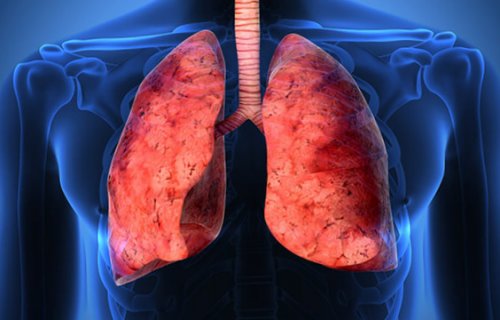

Рисунок 1. Фиброз легких. Источник: МедПортал

Грубые рубцовые волокна обладают низкой эластичностью (рис. 1). Они сдавливают бронхи, нарушают способность легких растягиваться при вдохе и сжиматься при выдохе. В результате этого нарушается дыхательная функция легких — процесс прохождения через альвеолярные стенки углекислого газа и кислорода.

Легкие человека состоят из миллионов альвеол — микроскопических пузырьков, в которых происходит обмен кислорода и углекислого газа между кровью и внешней средой. Их стенки образованы интерстициальной тканью. Длительные воспалительные заболевания могут приводить к необратимым изменениям в ней в виде фиброза — образования рубцов из соединительной ткани.оценить то, насколько вы восстановили

Патологический процесс разрастания в легких фиброзной (соединительной или рубцовой) ткани с постепенным замещением ею легочной альвеолярной ткани называют фиброзом. Процесс характеризуется постепенным снижением дыхательной функции вплоть до критического уровня. Ткань, образующая легкие, становится все менее эластичной и растяжимой. Уплотнение затрудняет газовый обмен: кислороду и углекислому газу становится сложнее проникать через стенки альвеол, способность легких к расширению постепенно теряется. В зависимости от локализации образования фиброзных участков и причин их появления зависит общее течение болезни.